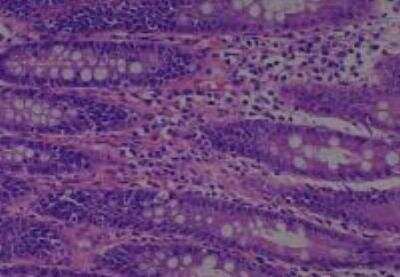

Hematoxylin & Eosin Stain: Human Common Tissue MicroArray (Normal Adjacent) [NBP2-30215] - 102. Stomach